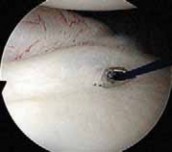

The surgical approach begins with the establishment of a standard posterior viewing portal, placed approximately 2 cm inferior and 1 cm medial to the posterolateral corner of the acromion. Upon entering the joint, a meticulous diagnostic sweep is performed. The surgeon must systematically evaluate the biceps anchor, the superior labrum, the articular surfaces of the humerus and glenoid, the rotator cuff footprint, and the entire capsulolabral complex. Particular attention is directed to the anteroinferior quadrant to confirm the presence of a Bankart or ALPSA lesion. The size and depth of any Hill-Sachs lesion are evaluated dynamically by taking the arm through a range of motion to assess for "engagement" over the anterior glenoid track.

Following the diagnostic sweep, two anterior working portals are established using an outside-in spinal needle localization technique. The anterosuperior portal is typically placed just anterior to the acromioclavicular joint, entering the joint through the rotator interval superior to the biceps tendon; this serves primarily for fluid management and suture retrieval. The critical anteroinferior working portal is placed just superior to the upper border of the subscapularis tendon, ensuring an optimal trajectory (approximately 45 degrees to the glenoid face) for anchor insertion along the anteroinferior glenoid rim. A clear cannula (typically 5.5 mm or 8.25 mm) is introduced to facilitate smooth instrument passage and suture management.